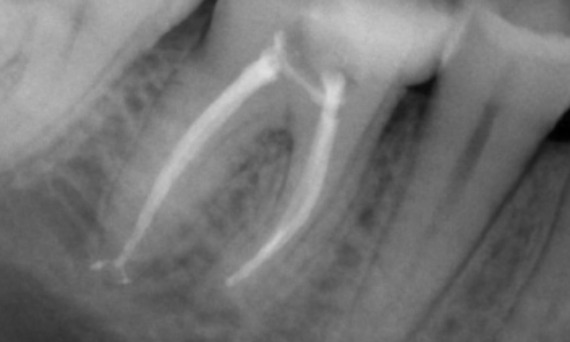

Avant : L’examen a révélé une lésion carieuse liée à la première molaire mandibulaire droite. L’examen radiographique a révélé la proximité de la lésion avec la corne pulpaire et, en l’associant à la plainte principale, un diagnostic final de pulpite chronique irréversible a été posé.

Après : La cavité d’accès a été réalisée de la manière la plus conservatrice possible. TruNatomy a été le système de choix en raison de l’âge du jeune patient. Nous devions préserver la dentine autant que possible afin d’augmenter la capacité de la dent à surmonter la charge occlusale et d’accroître la longévité de la restauration finale.